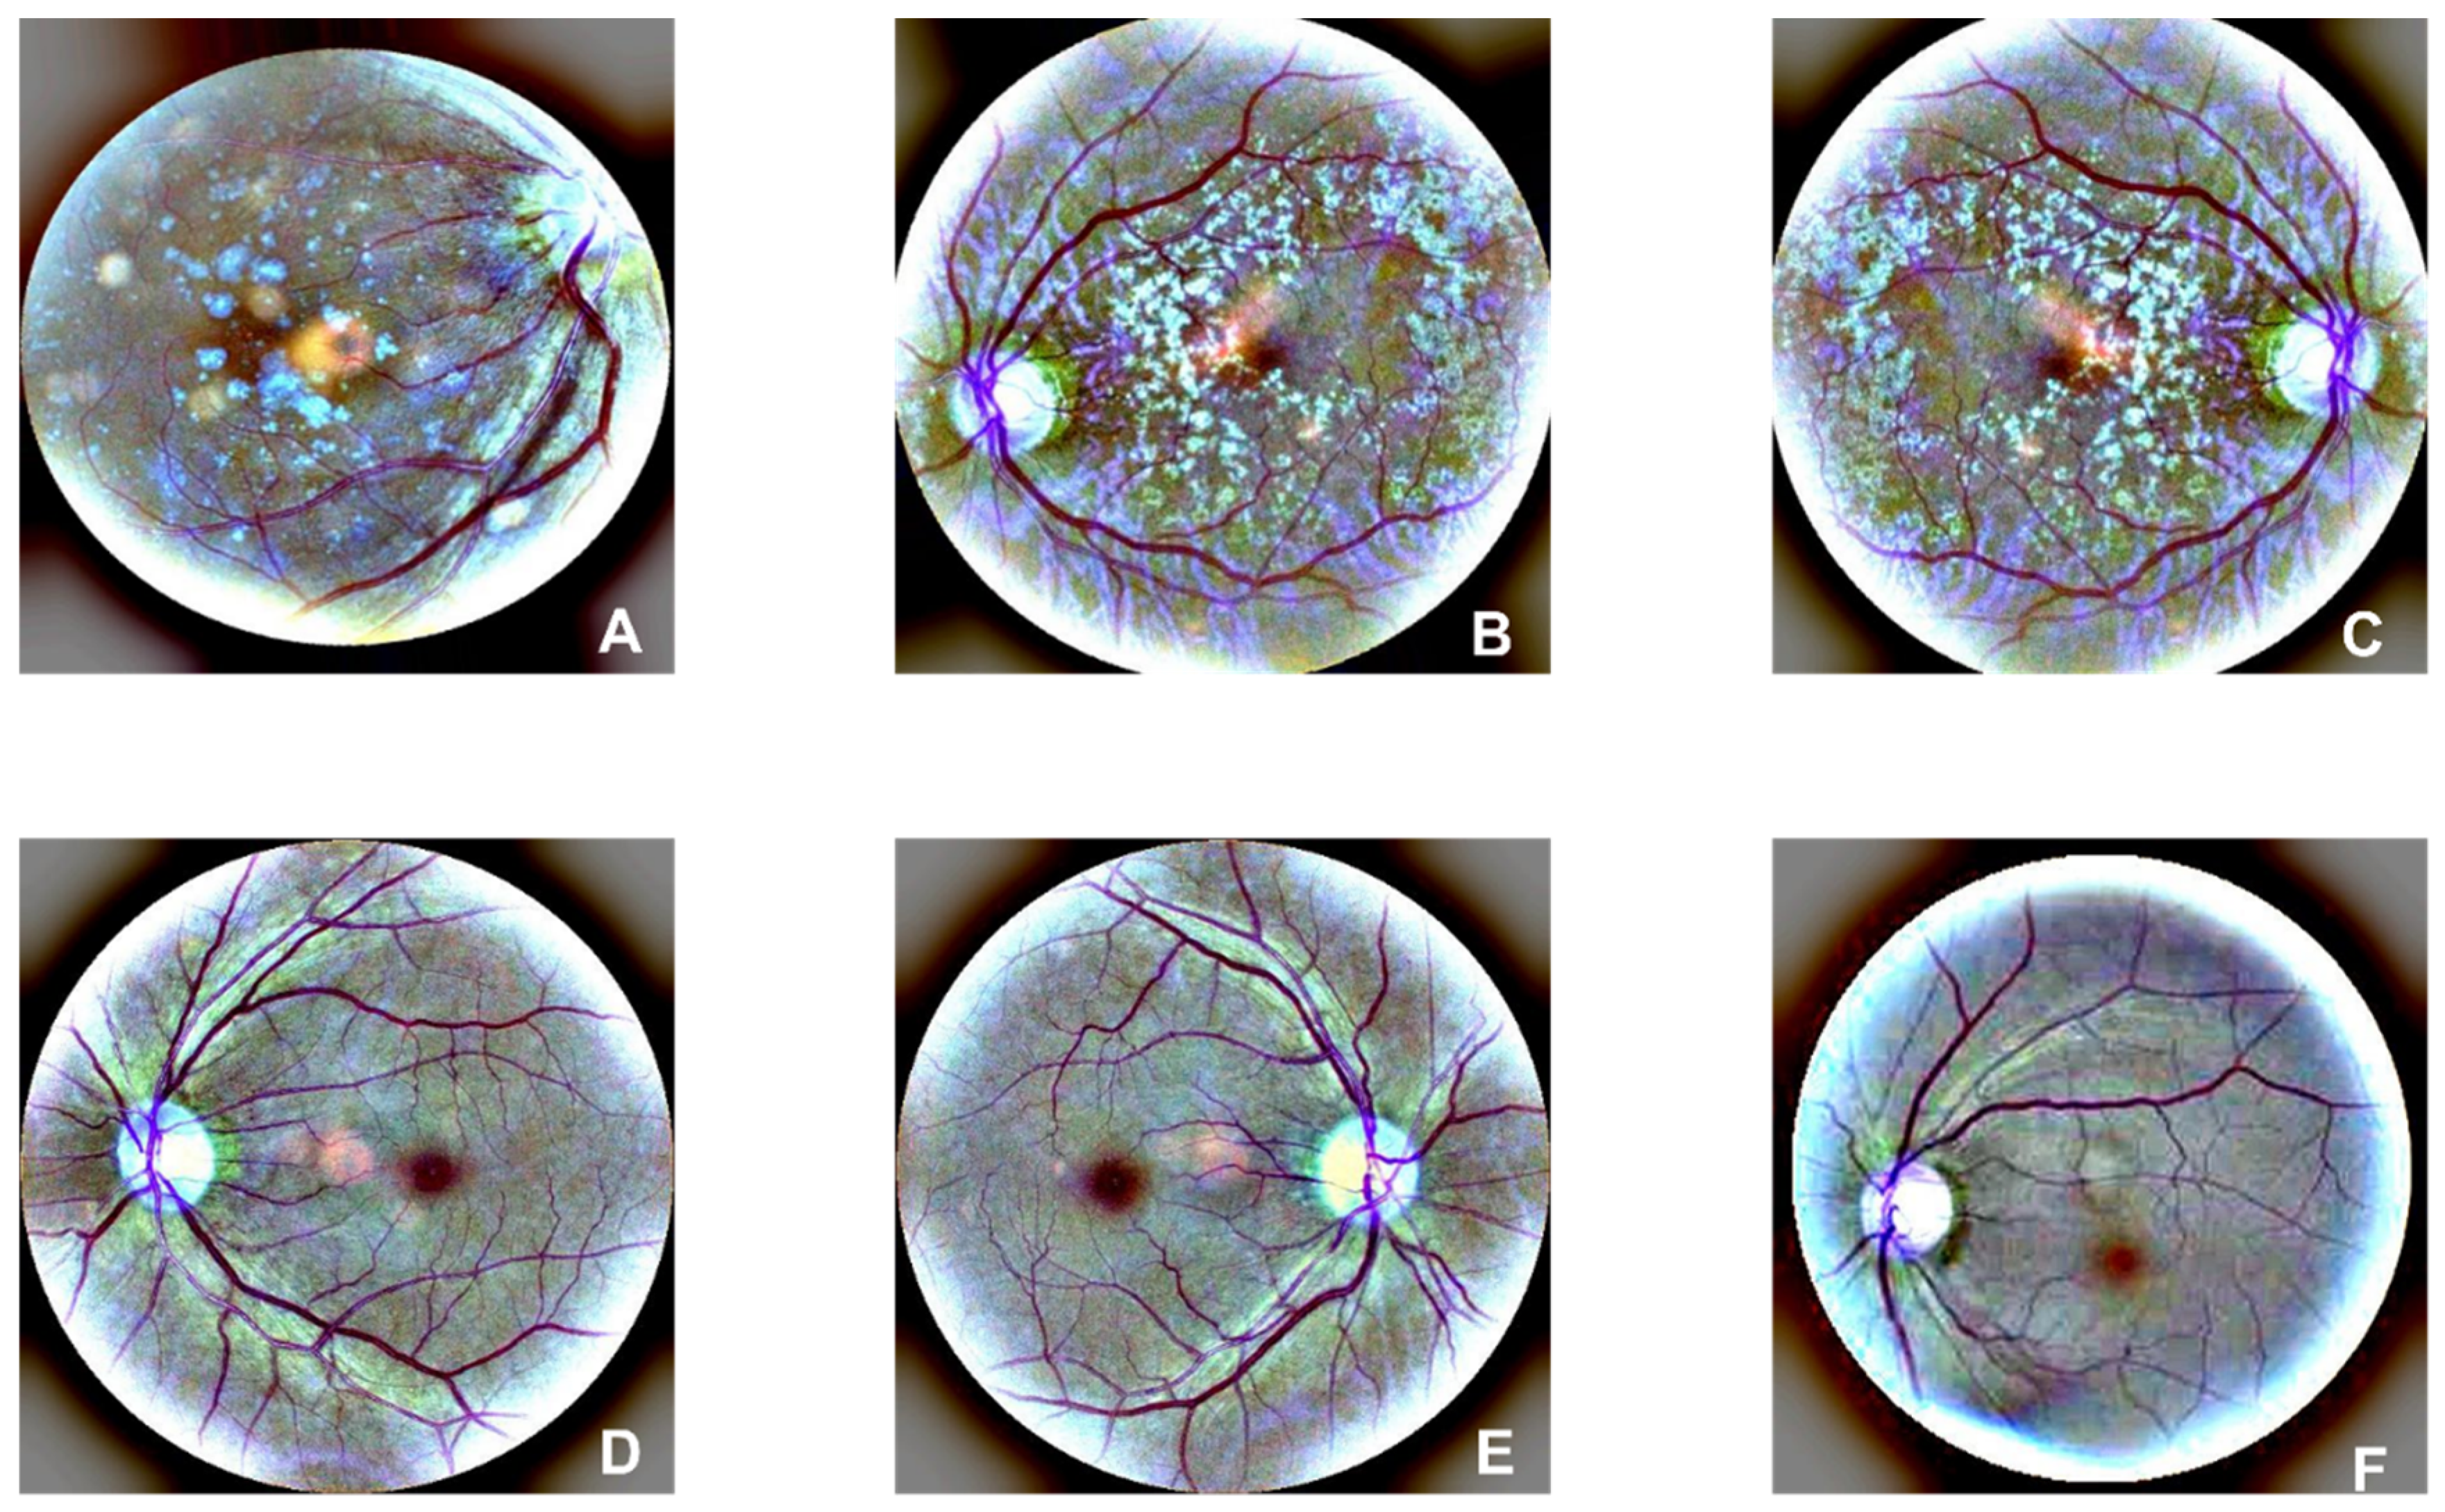

Figure 1 is an example of OCT original figures, where A, B, and C are related to AMD cases, and D, E, and F belong to normal clusters. The symptom of drusen is presented in AMD images. To solve the imbalance issue between the numbers of negative(29347) and positive(3000) subjects in the training dataset, a data enhancement process is performed on the AMD pictures, which includes image rotating[

Figure 1.

Original figures of OCT images. Subfigures of D, E, and F are related to normal subjects. Subfigures of A, B, and C are related to the AMD subjects with drusen on choroid retina.